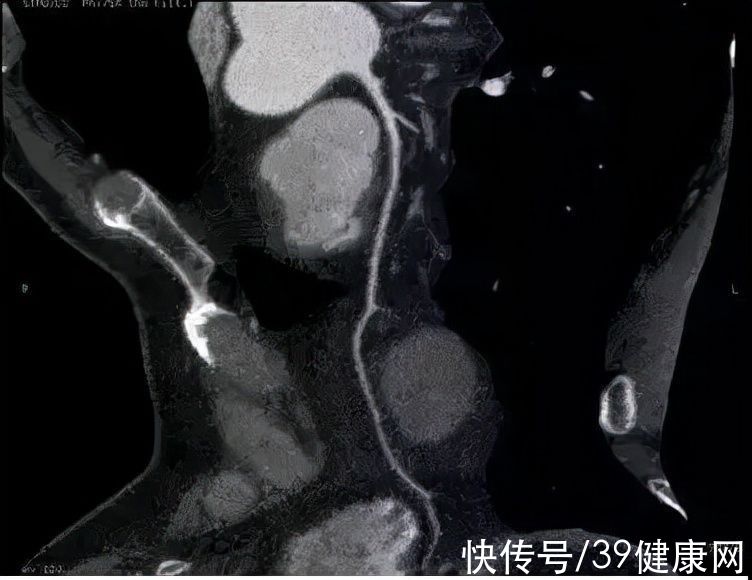

检查结果出来,周主任看到后十分惊讶——前降支近端狭窄消失了,血管光滑了,斑块也不见了。周主任仔细观察各层面的影像,的确没有发现任何斑块。

老王现在的片子 图源:周大亮医生